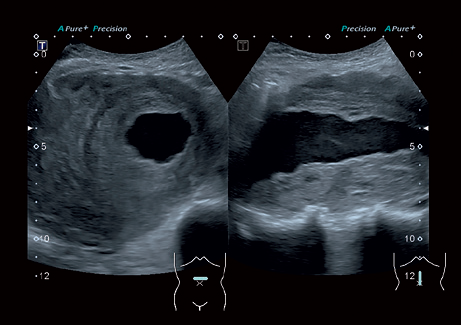

• Precision Imaging - технология получения изображений мелких деталей с четко очерченными границами и высокой однородностью

Precision Imaging:

Да

• Прецизионная визуализация (Precision Imaging) для послойного дифференцирования тканевых структур и высокой детализации;